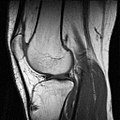

-

MRT-Kniegelenksaufnahme (sagittales Schnittbild)